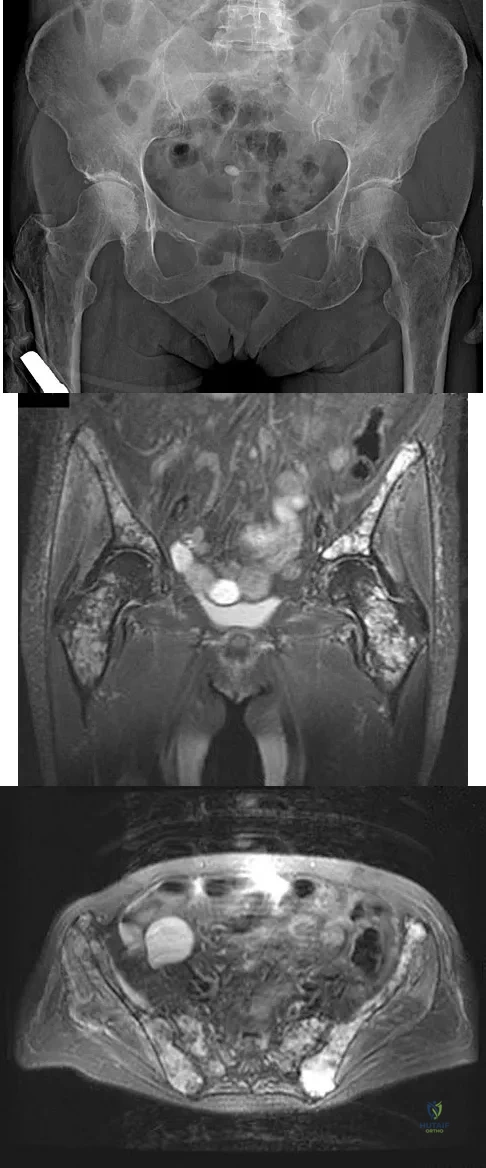

A 62-year-old woman reports diffuse aches and pains of the hip and pelvis. She denies any significant trauma but does have a history of chronic anemia. Figure 17a shows a radiograph of the pelvis, and Figures 17b and 17c show T2-weighted MRI scans. What is the most likely diagnosis?

Explanation